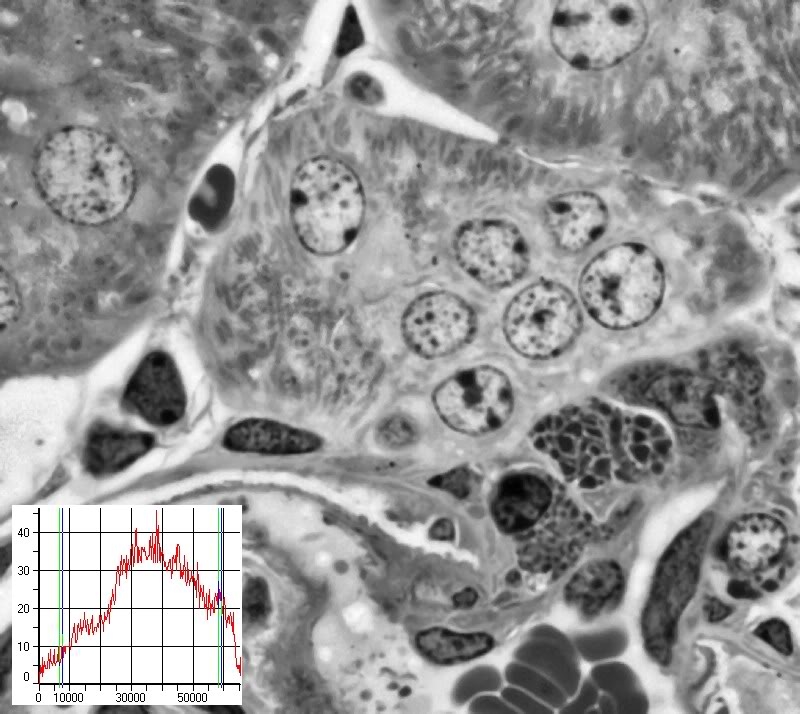

Bild 26b zeigt das gleiche Bild, nun aber nach Anwendung einer Kontrastverbesserung basierend auf lokalen Kriterien.

Das in der unteren Ecke angegebene Histogramm zeigt, dass trotz der differenzierten Kontraststeigerung kein nennenswertes Clipping entstanden ist.

Das Bild weist nun sehr guten Kontrast in hellen, mittleren und dunklen Partien auf ! Viele Details, wie z.B. die Mitochondrien in der mittleren Zelle, sind deutlich besser sichtbar.